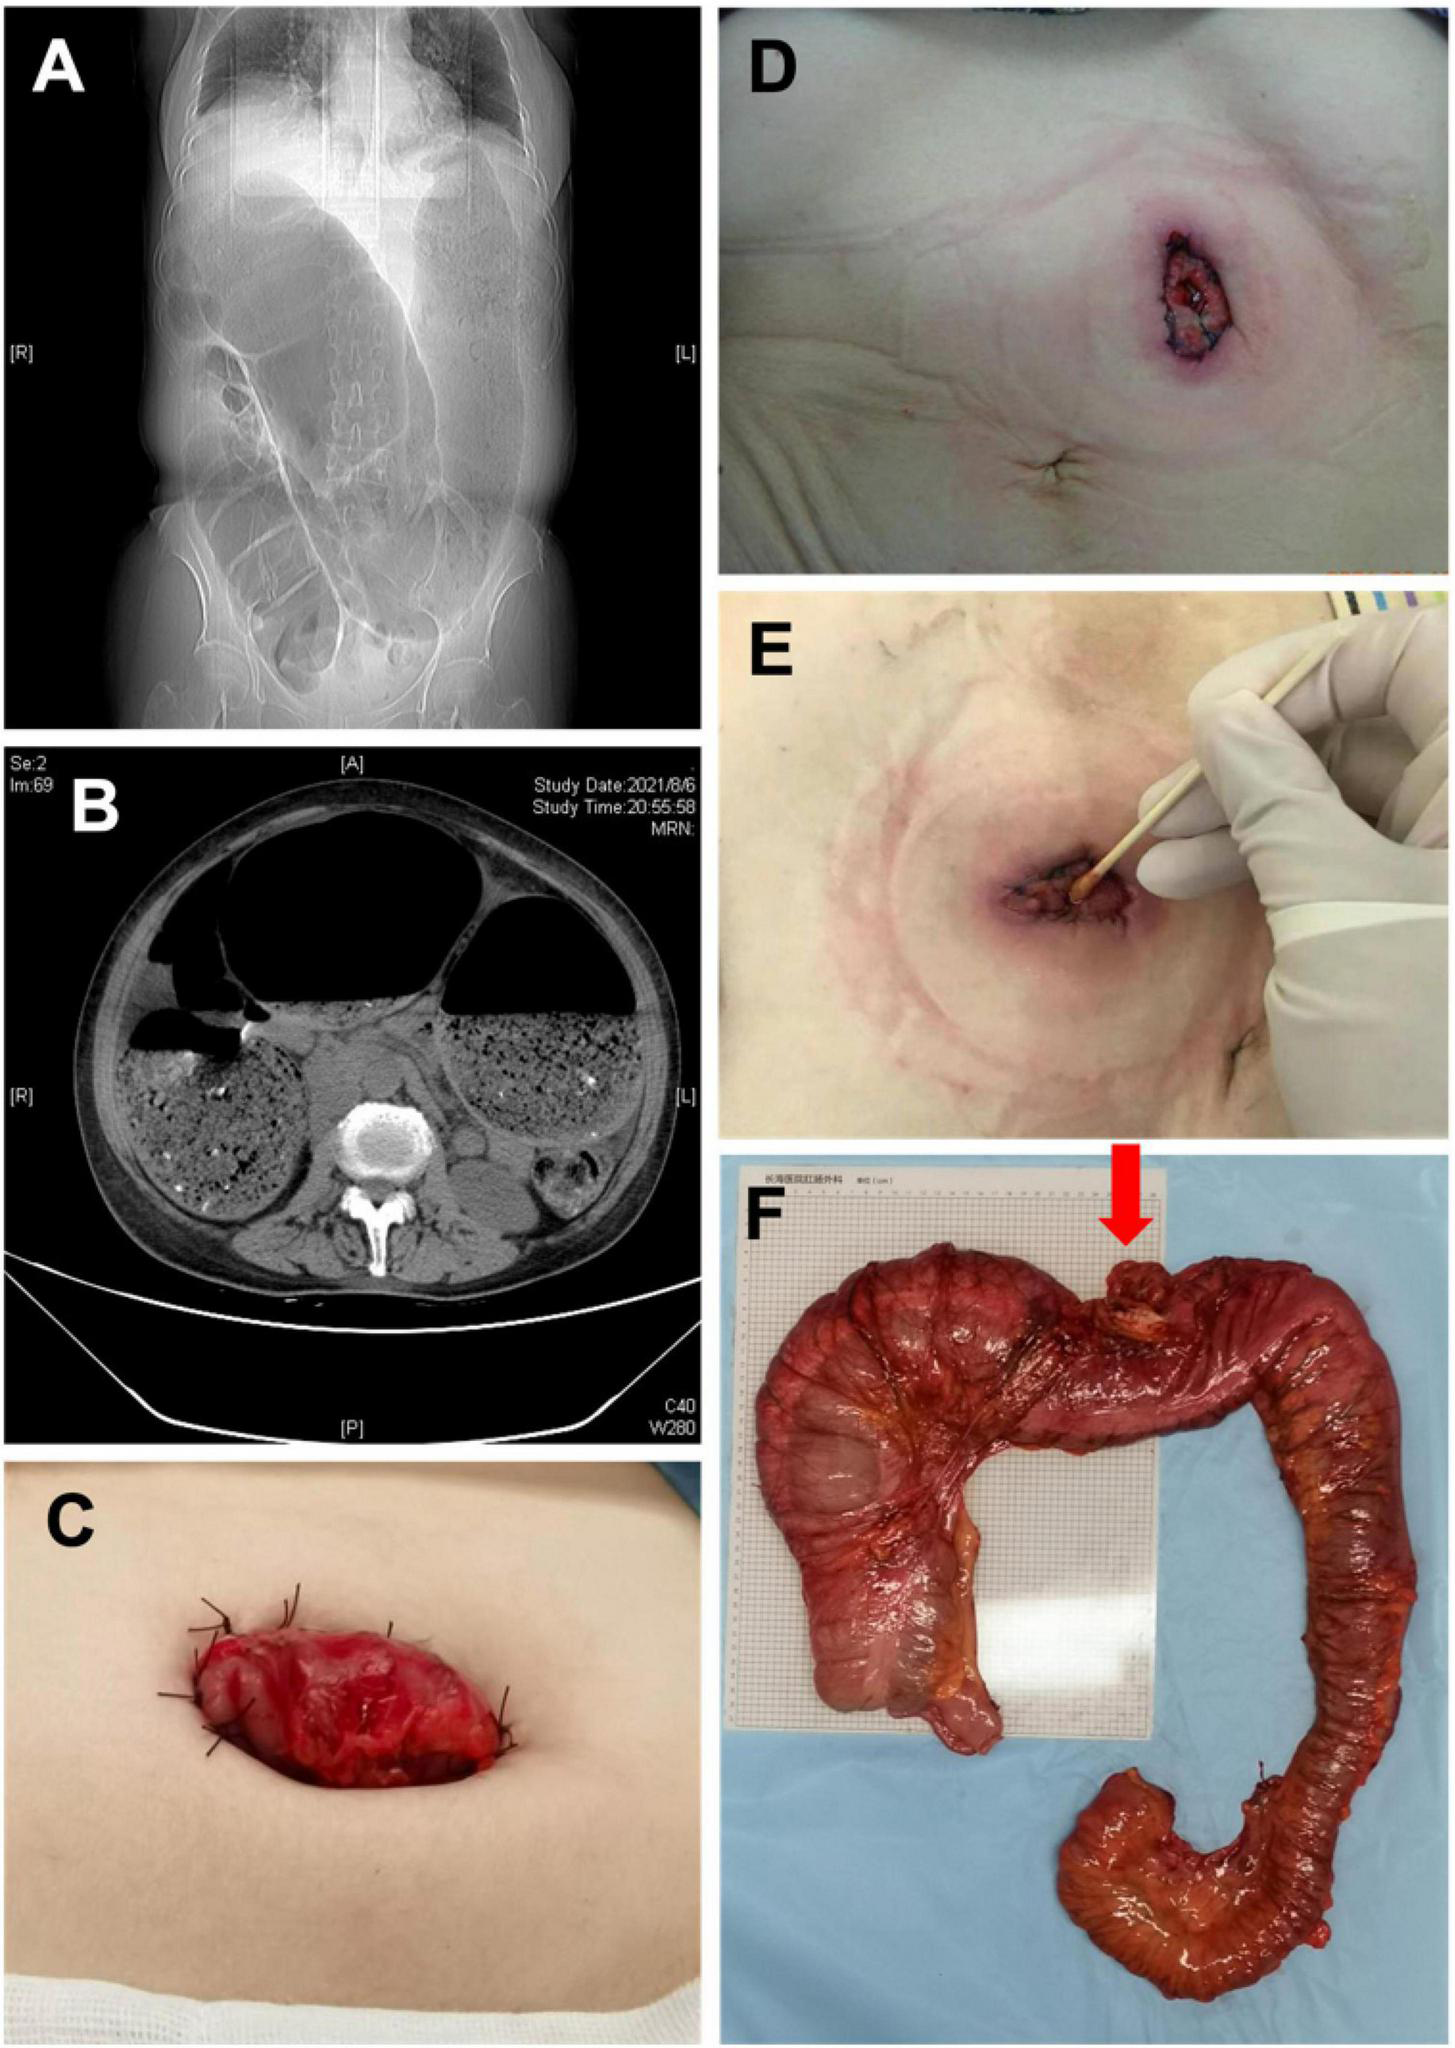

Thirty-five patients were diagnosed with idiopathic megacolon before surgery. Selective surgical treatment was conducted in 24 patients, which was subtotal colon resection with ileal rectal anastomosis or ascending colorectal anastomosis. Eleven cases were admitted to hospital with emergency bowel obstruction, accounting for 31.4% of patients with idiopathic megacolon. Among them, five cases were treated conservatively or selective surgery after colonoscopic decompression. The other six cases were treated by ostomy surgery. The loop colostomy cannot be performed in those six patients due to the ostomy bowel segment was extremely dilated, a transverse colon fenestration colostomy was performed. Unfortunately, various degrees of stoma stenosis occurred after the operation in those patients, only a cotton swab can be passed through the stoma in severe cases. All six patients with stoma underwent second-stage surgery, which was subtotal colon resection with ileorectal anastomosis or ascending colorectal anastomosis, and the stoma was removed at the same time (Figure 2).

FIGURE 2

(A) X-ray image manifestations of adult idiopathic megacolon; (B) CT image of adult idiopathic megacolon; (C) photos after colostomy; (D) 1 week after colostomy; (E) 1 month after colostomy; (F) the intestine specimen after subtotal resection (Red arrow: transverse colostomy).